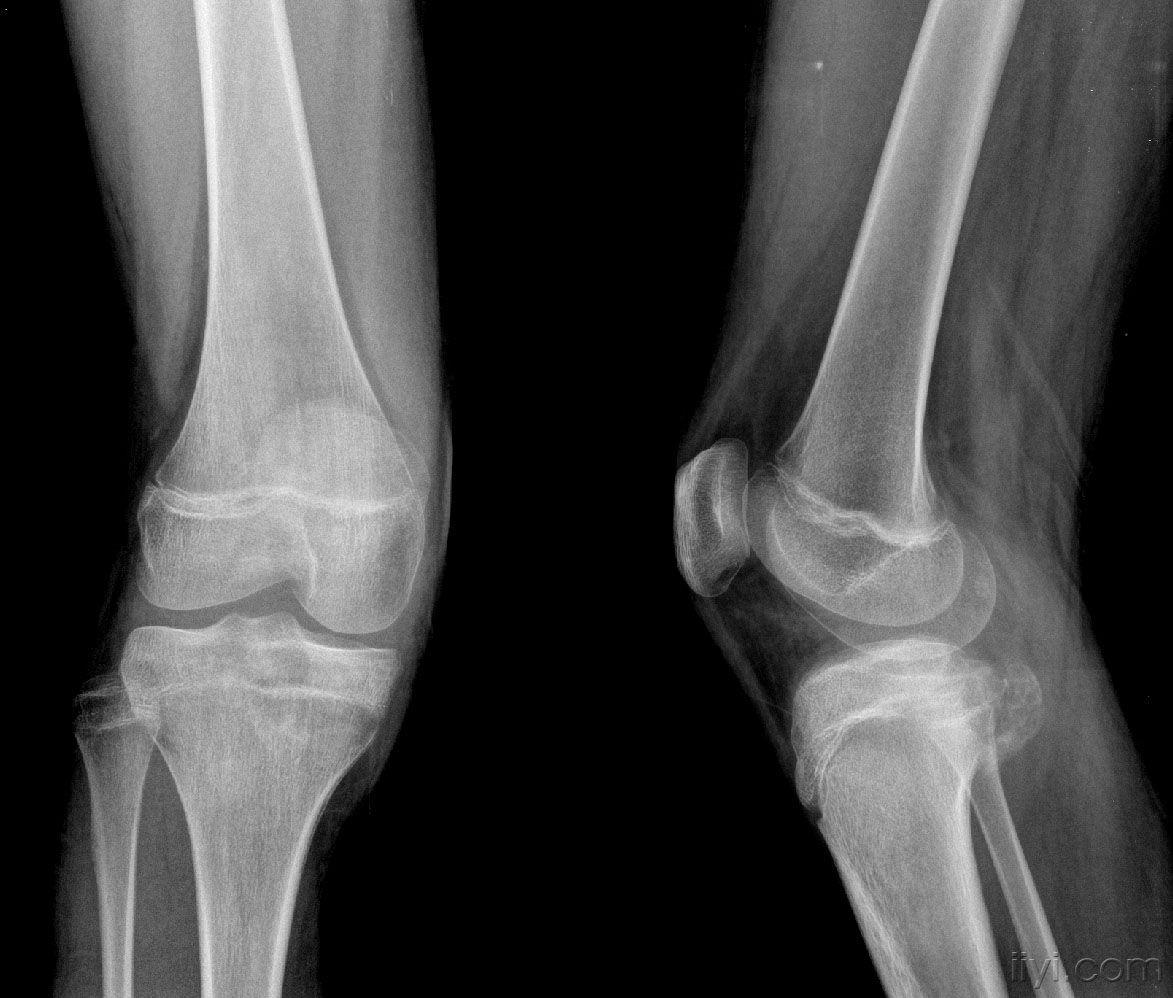

女,14岁,膝关节外伤后疼痛4月余。